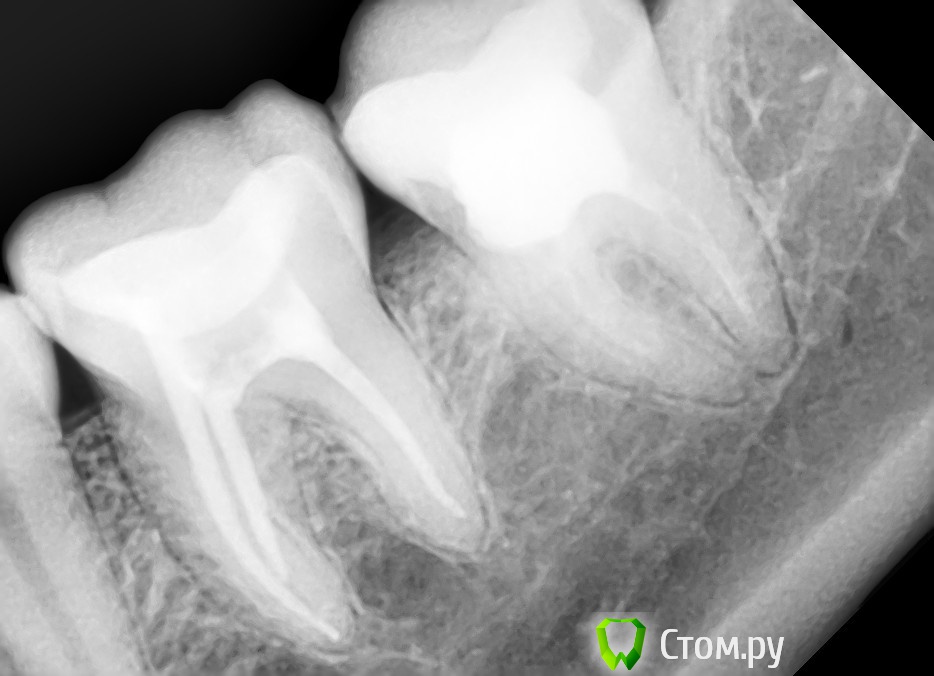

july88 Опубликовано 1 октября, 2014 Поделиться Опубликовано 1 октября, 2014 (изменено) Добрый день!Подскажите пож-та нужно ли перелечивать каналы на семерке?Зуб был депульпирован 7-8 лет назад.Сейчас неприятные ощущения при постукивании и чешется десна между 6 и 7.Иногда зуб ноет, но непонятно 6 или 7...6 зуб был вылечен от пульпита 1,5 мес назад.после лечения болел долго и реагировал на холод (пропила нимесил 5 дней, стало лучше), но и сейчас иногда бывают неприятные ощущения, также боль отдает в верхнюю 6 (глубокий кариес был вылечен в июле) Доктор говорит что это из-за воспаления на 7. Изменено 1 октября, 2014 пользователем july88 Ссылка на комментарий

july88 Опубликовано 17 ноября, 2014 Автор Поделиться Опубликовано 17 ноября, 2014 перелечили мне каналы в 7 зубе, также доктор нашел дополнительный. Была сильная боль после нахождения 3-го канала, доктор положил кальциевую пасту на 2 нед., боль сразу прошла и через 2 недели мне полностью запломбировали каналы гутаперчей. На контрольном снимке все было отлично, доктор сказал запаха не было. Прошло 3 нед и боль вернулась, зуб ужасно чешется внутри и болит.Нужно ли заново лезть в каналы или просто удалить его?что так может беспокоить?Доктор не знает что со мной делать... Ссылка на комментарий